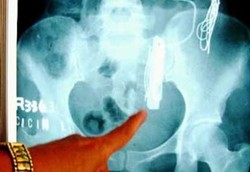

Pensiun Makan Logam Setelah Tersedak Pedal Sepeda

Pria ini sudah mengonsumsi 25.000 bola lampu, 12.000 garpu, 2.000 sendok, 2.600 piring dan hampir 6.000 piringan hitam vinil. Tapi di usia 80 tahun ia pensiun makan logam karena hampir meninggal setelah tersedak pedal sepeda.